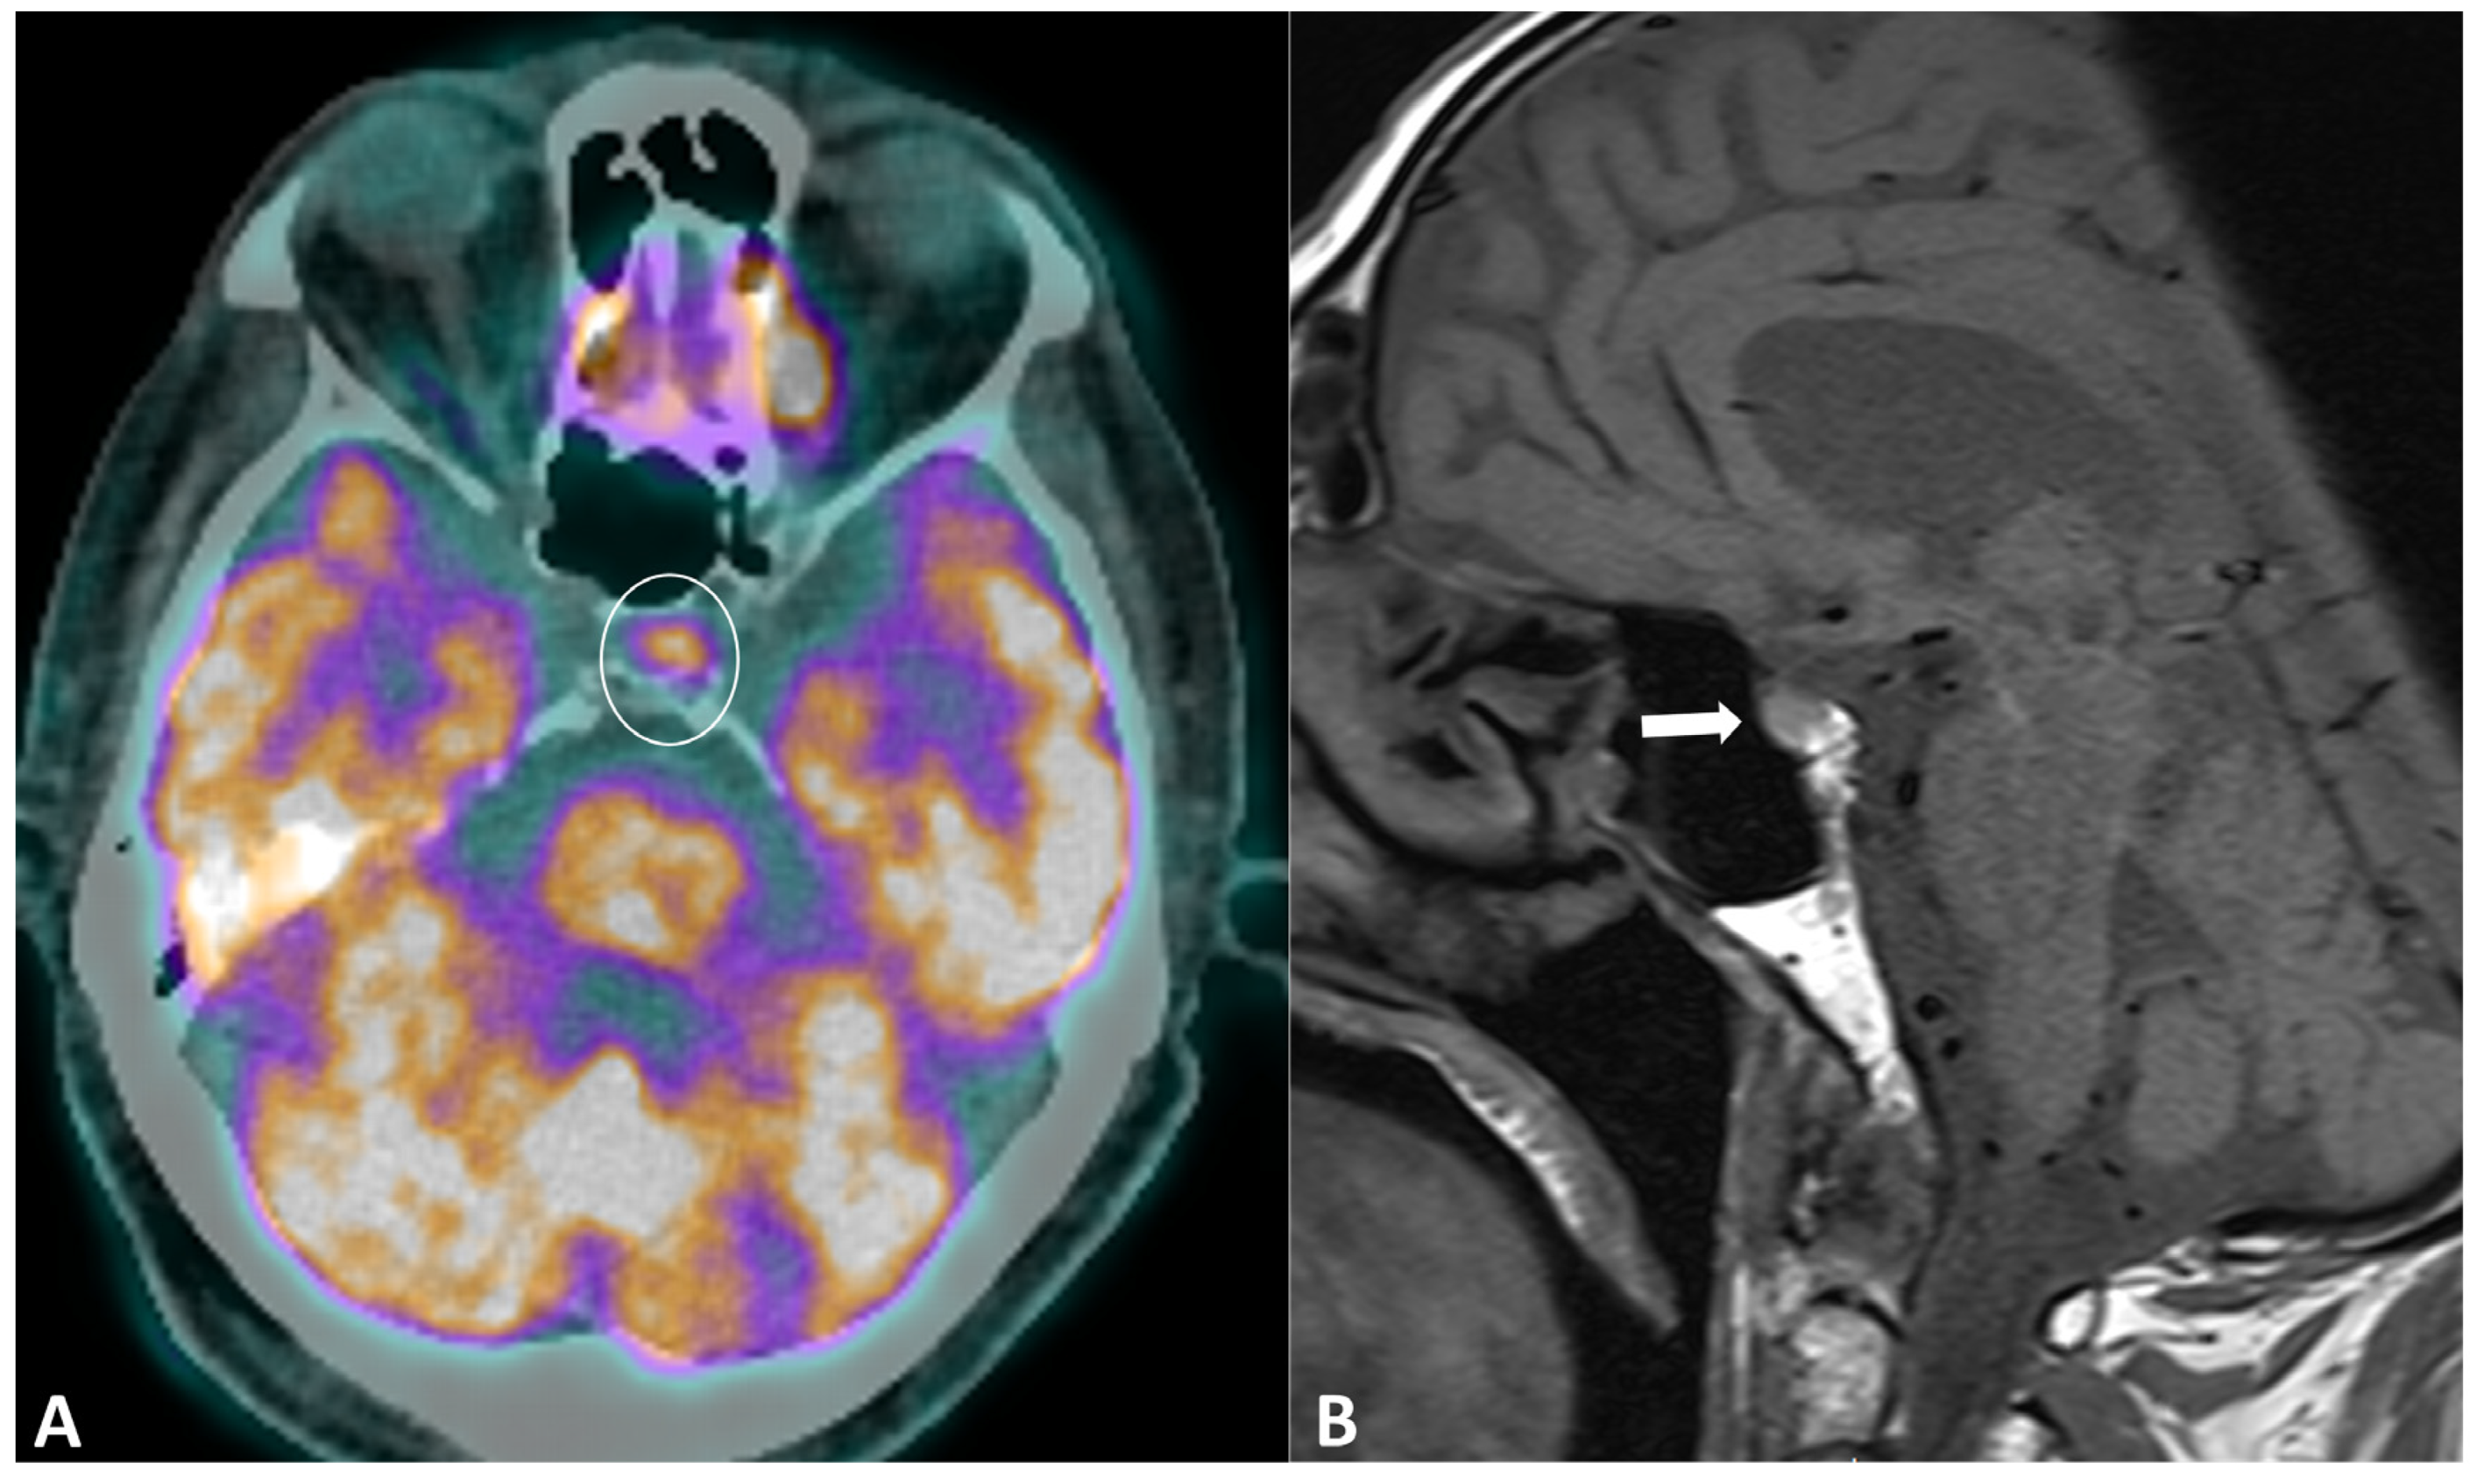

Hypophysitis is an ICI complication, occurring in 0.1% to 18% of patients, depending on the type of treatment [91]. The clinical presentation is nonspecific, with symptoms derived from decreased cortisol (fatigue, appetite loss, nausea, vomiting, malaise, dizziness, and mild cognitive defects) being far more common than in primary hypophysitis [92]. The diagnostic workup usually includes hormonal axes evaluation and hypophysis MRI. Pituitary biopsy is not necessary, it is rarely performed in case of alternative diagnosis (metastasis) suspicion. MRI protocol includes T1w and T2w sequences with small FOV in coronal and sagittal planes for assessing size and anatomical details, followed by dynamic T1w acquisitions after gadolinium contrast agent injection at multiple time points using small FOV. MRI can be normal in up to 30% of cases [92]. When pathological, the key finding is a diffuse and transient enlargement of the pituitary gland (Figure 9). The enhancement pattern can be variable, either homogenous [93] or geographic with a reduced enhancement of the antehypophysis [94]. The pituitary stalk can also be thickened. The differential diagnosis includes pituitary metastasis and adenoma. The most reliable elements for the differential diagnosis are the regression of the enlargement after treatment interruption and, for metastasis, the absence of invasion and destruction of neighboring structures. Typically, ir-hypohysitis shows intense FDG uptake at PET/CT and its detection may precede symptoms (Figure 9).

Figure 9.

Immune-related hypophysitis in a patient with metastatic lung cancer treated with combined antiPD-1 + antiCTLA-4. A restaging PET/CT (A) showed the appearance of a moderate uptake of the hypophysis (circle). An MRI was then performed, revealing (B) a slight hypophyseal enlargement with homogeneous enhancement (arrow), without significative pituitary stalk thickening noroptic chiasm compression. The hormonal tests were unremarkable, and thus compatible with a grade-1 hypophysitis. ICI treatment was temporally discontinued to ensure the regression of the metabolic activity and the absence of delayed clinical or biological signs, then rechallenged with no recurrence of the hypophysitis.